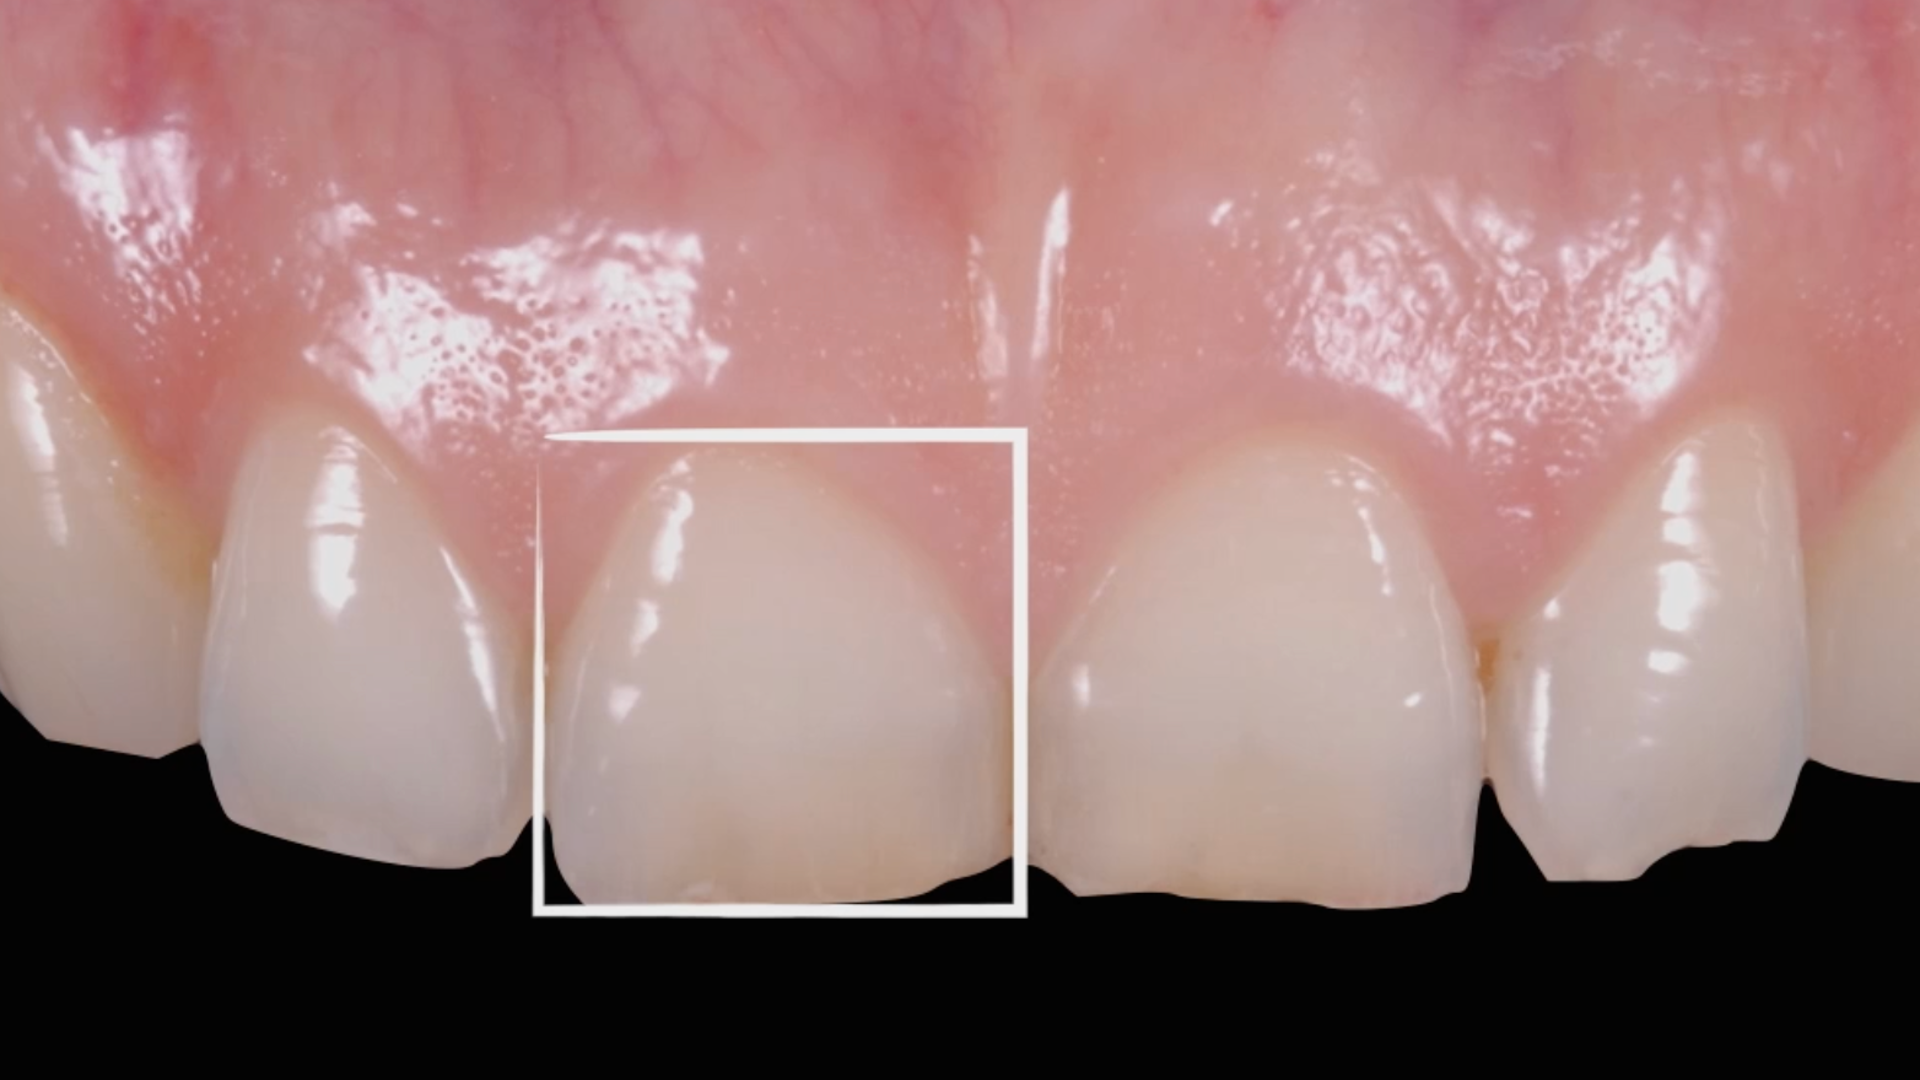

MIPP 0: clinical cases and No-prep veneers procedures

Clinical case - MIPP 1: conventional buccal veneers procedures

MIPP 2: the new concept behind Full-Veneers to optimise aesthetics and functionality

MIPP 2B: clinical case of Full-Veneers in openbite with preserved enamel tooth structure

MIPP 2: MIPP 2A and MIPP 2B combined technique